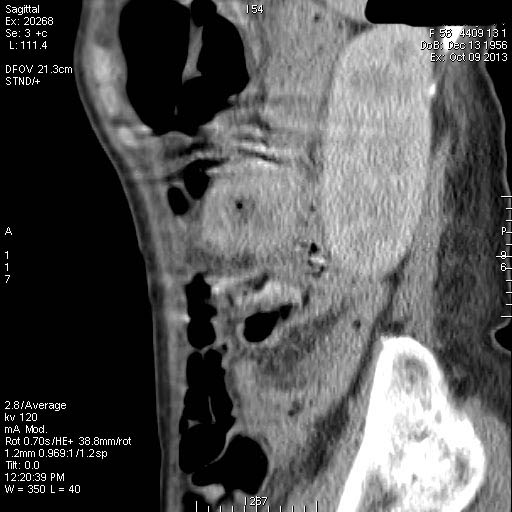

Женщина средних лет поступила в хирургическое отделение с кишечным кровотечением.

Пальпируется образование в мезогастриуме слева. При УЗИ определяется тумор, не связанный с толстой кишкой.

КТ

Операция - обнаружена опухоль тонкой кишки, предположительно гемангиома, выполнена резекция части кишки.

Гистологический ответ - GIST.

GIST тонкой кишки